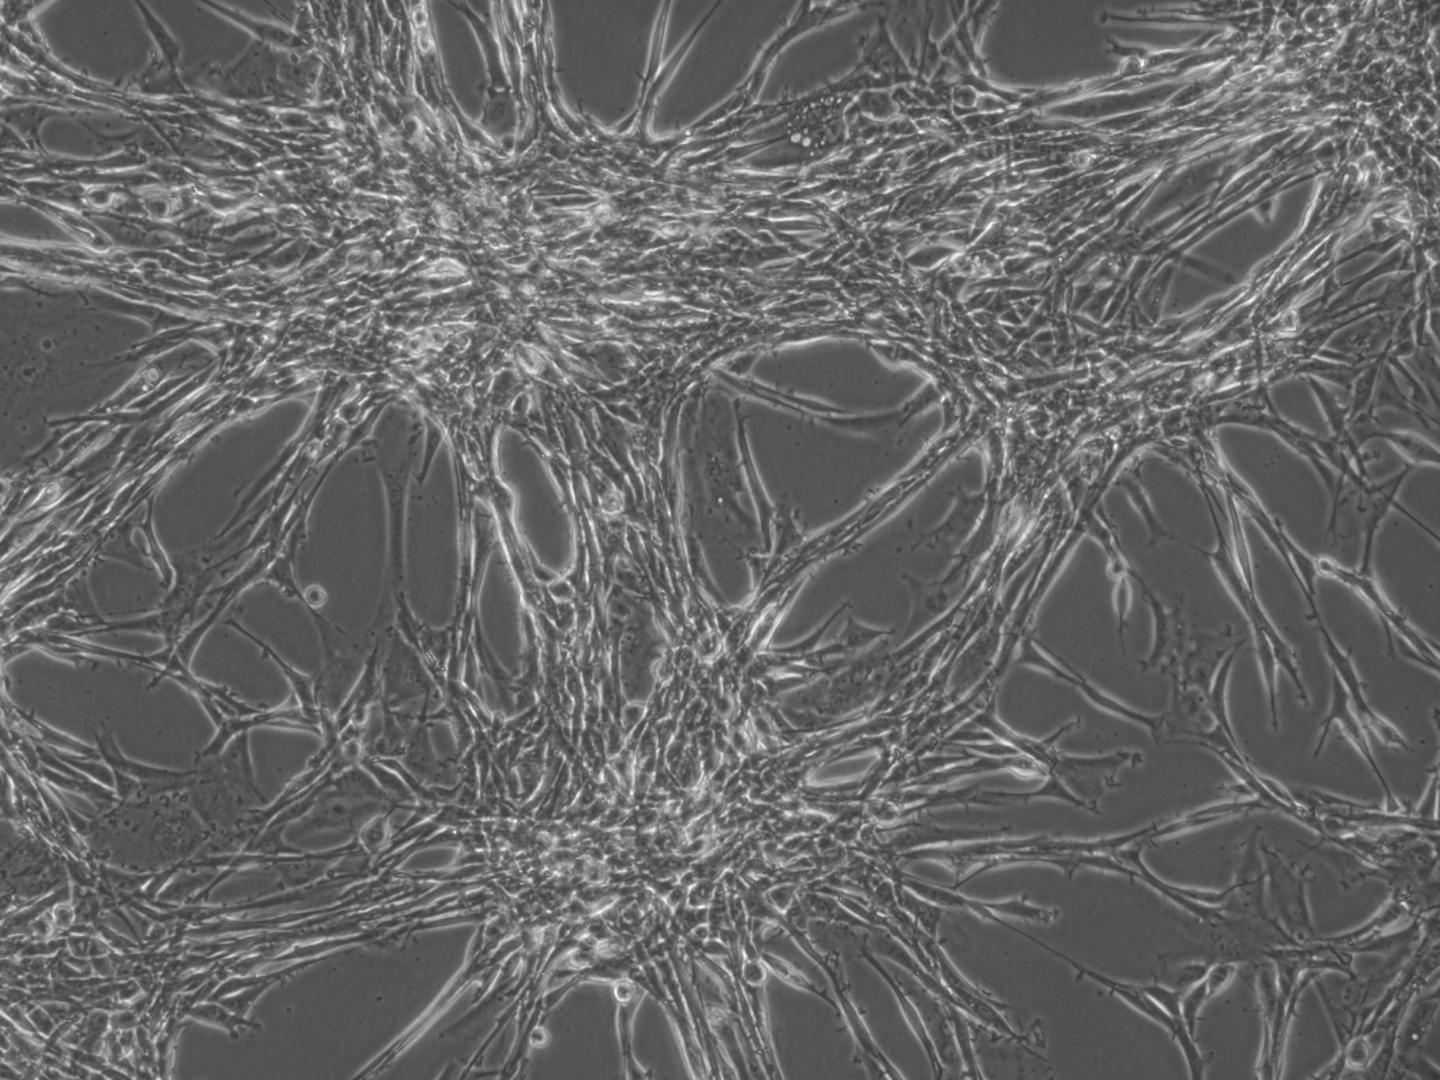

image: Glioblastoma Multiforme (GBM) cells in culture (Photo: Jin-Min Nam)

Scientists have identified key molecules that mediate radioresistance in glioblastoma multiforme; these molecules are a potential target for the treatment of this brain cancer.

Glioblastoma multiforme (GBM), is the most aggressive type of brain cancer. It is treated by radiation therapy combined with chemotherapy. However, even with treatment, the five-year survival rate for GBM is less than 7%. One of the major causes for this is that GBM rapidly develops radioresistance (resistance to radiotherapy) by unknown mechanisms.